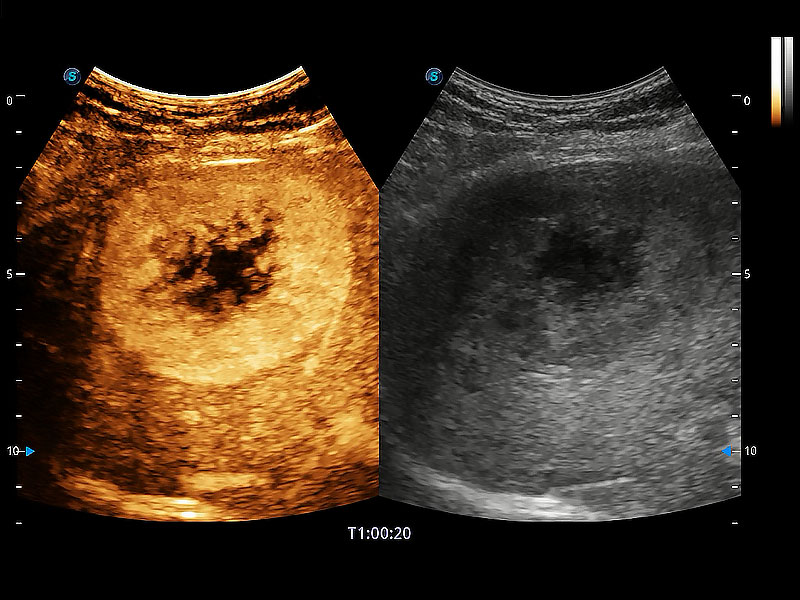

非線性融合造影成像充分利用諧波和基波信號,為難以觀察的血流進行增強顯像。可用于線陣、凸陣、微凸陣、相控陣探頭。

極大提升超低速微細血流的檢出能力,同時更精準地濾除軟組織和超聲信號,為獸用醫(yī)生提供以往無法通過常規(guī)血流獲得的疾病診斷信息。

在傳統(tǒng)二維血流成像的基礎(chǔ)上,呈現(xiàn)血流的立體感,具有動感的生命力之美。即便是微小的血管也能輕松應(yīng)對,提高了血流的視覺敏感性。